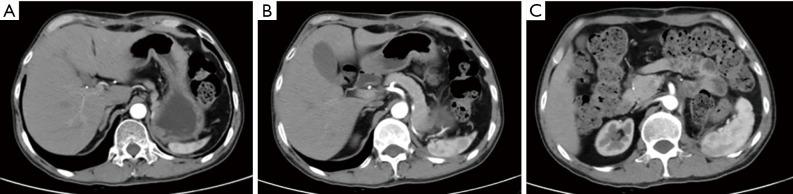

This is the first case report of the outcomes of systemic chemotherapy in a patient with locally advanced renal squamous cell carcinoma, a rare tumor, as well as the first next generation sequencing study of this rare tumor. The patient's main symptoms were fever and low back pain. Initial positron emission tomography and computed tomography (PET-CT) suggested a malignant renal tumor at onset, but biopsy confirmed renal squamous cell carcinoma. Next generation sequencing showed a low level of microsatellite instability (MSI-L), a high tumor mutational burden (TMB-H), a high neoantigen burden (TNB-H), and a strong loss of heterozygosity (LOH) for human leukocyte antigen (HLA), with 67 deleterious mutations. The patient achieved partial radiological remission after a cycle of systemic chemotherapy with albumin-bound paclitaxel combined with nedaplatin. After radical resection of the left renal tumor, postoperative pathology confirmed complete tumor remission and tumor-like xanthogranulomatous pyelonephritis. Conclusion: This renal squamous cell carcinoma patient responded to systemic chemotherapy with paclitaxel combined with platinum, providing a reference for the future treatment of similar cases. Pathology and gene sequencing indicated that renal squamous cell carcinoma occurred in a background of active inflammation and that the tumor evolved immune escape mechanisms such as loss of HLA heterozygosity, with gene repair defects and TMB-H.

这是首例关于局部晚期肾鳞状细胞癌(一种罕见肿瘤)患者全身化疗结果的病例报告,也是该罕见肿瘤的首例二代测序研究。患者的主要症状为发热和腰痛。初始正电子发射断层扫描和计算机断层扫描(PET-CT)显示起病时为恶性肾肿瘤,但活检确诊为肾鳞状细胞癌。二代测序显示微卫星不稳定性水平低(MSI-L)、肿瘤突变负荷高(TMB-H)、新抗原负荷高(TNB-H)以及人类白细胞抗原(HLA)杂合性缺失严重(LOH),有67个有害突变。患者在接受白蛋白结合型紫杉醇联合奈达铂的全身化疗一个周期后实现了部分影像学缓解。左肾肿瘤根治性切除术后,术后病理证实肿瘤完全缓解以及肿瘤样黄色肉芽肿性肾盂肾炎。结论:该肾鳞状细胞癌患者对紫杉醇联合铂类的全身化疗有反应,为未来类似病例的治疗提供了参考。病理和基因测序表明,肾鳞状细胞癌发生于活跃炎症背景下,且肿瘤演化出了免疫逃逸机制,如HLA杂合性缺失、基因修复缺陷和TMB-H。